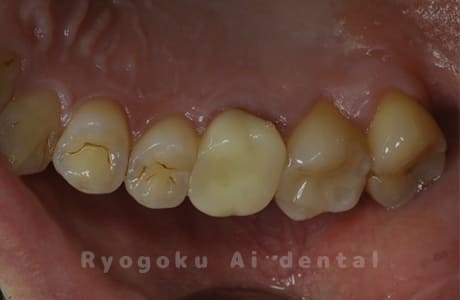

Case03

- 重度カリエス、慢性根尖性歯周炎

- 治療内容

- 自家歯牙移植

- 治療費用

- 220,000円

他院で右下の根の治療を行い、セラミックを被せる説明をされていたが、根の治療が終わらないため転院された患者さんです。隣の親知らずの抜歯の必要性と、根の治療を行なっている歯牙の予後が悪いため、移植治療を提案し、右下の親知らずの抜歯と同時に、右下の奥歯(7番)への移植治療を行いました。被せ物を行う必要もなく、順調に経過してます。

<リスク・副作用>

治療後、痛みや違和感、出血、腫れなどが出る事があります。喫煙者、糖尿病などの方の場合、歯が生着しない場合があります。